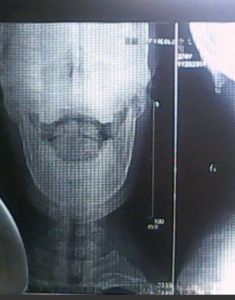

人的頭骨形狀和骨塊的數量基本是相同的、沒有任何人的後腦頭骨多長了一塊、或是長出了一塊以別不同的頭骨來。腦後反骨只是一句概念化的東西,沒有實質性的物體可言。那么、相學上的所謂腦後有反骨、這個反骨究竟是什麼?從相學書籍里查找、找不出有類象的文字描述、也沒有見過腦後反骨的頭相圖形。硬要從後腦勻去探索這個反骨、的確無從下手。偶有個別古今相學愛好者推測、腦後見腮即是腦後見反骨。這個說法、是有道理的。

腦後見腮、指的是臉上下巴兩側的腮骨相對擴張、橫出、甚至骨角明顯。就是從背後看、也能明顯看得見腮骨的銳角、這就是腦後見腮、或者稱為;反過來看也見骨。貶義的說法就是腦後見反骨。腦後反骨、腦後見腮的臉形不少。